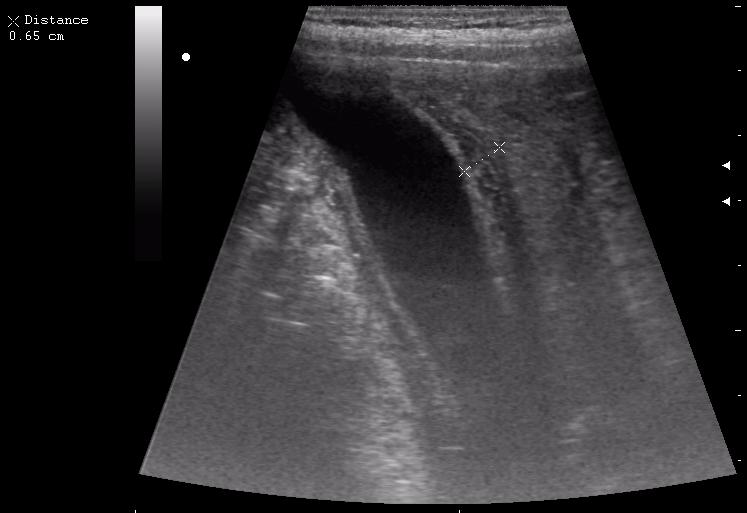

сегодня был селезёночный день.

мальчик лежал на спине (переломы костей таза). на затёки крови не похоже.